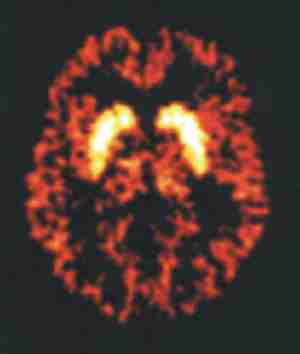

NMR und PET

VIII: Darstellung des Gehirns butmeth.jpg

nmrin.jpg petin.jpg